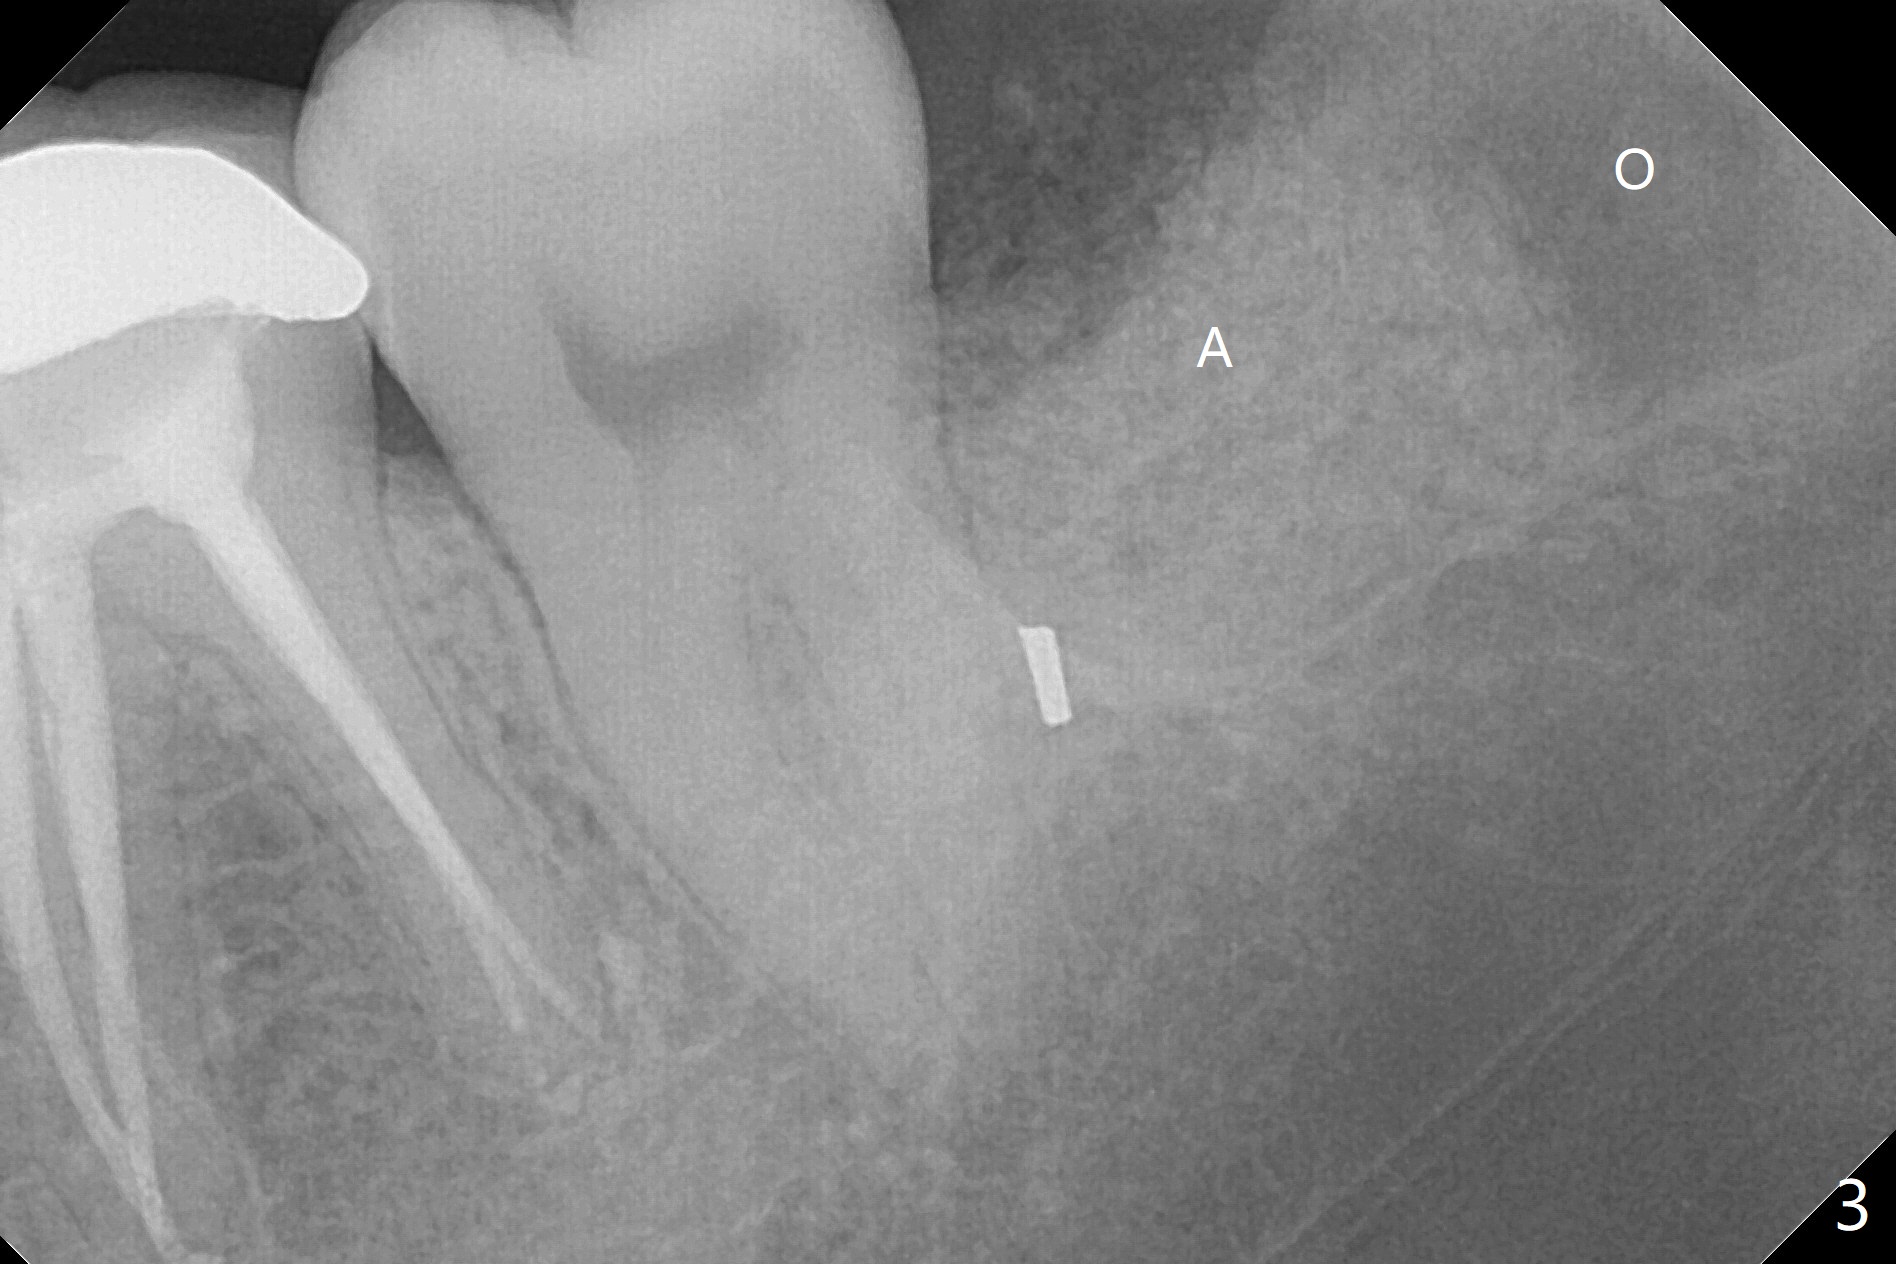

A 41-year-old woman (dental phobic) requests extraction of the tooth #17 because of food impaction (Fig.1). The fractured root tip (Fig.2 *) is so deep that the longest surgical length fissure bur can not reach in spite of multiple sectioning. The nervous patient agrees not to remove the root tip because of pain associated with root tip loosening. The fractured bur tip cannot be found clinically. CBCT should have taken for bur location and the proximity of the root tip to the Inferior Alveolar Canal. To prevent dry socket, Osteogen Plug is placed in the radicular portion of the socket (Fig.3 O), while allograft (A) in the coronal part of the socket. With Collagen Plug placed superficial to the allograft, 4-0 plain gut suture is used to close the socket. The patient returns 11 days postop with chief complaint of "pain returns for 2 days, affecting sleep. Small particles came out". #17 gingiva is healthy, although there is tenderness on deep palpation of #17 D. There is no exudate. Chlorhexidine irrigation is done with 2 syringes with pain relief. Augmentin is prescribed for 7 days. Pain disappears in ~ 1 month. Bone fills the socket 1 year postop (Fig.4).